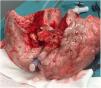

In this case, the full flow was attained after 60min of perfusion. However, we observed a high PA pressure, pulmonary vascular resistance, and low dynamic lung compliance. The grafts were discharged due to a copious amount of frothy pink sputum and an impaired collapse test (Figs. 1 and 2).

A 20-year-old woman with a history of obesity and oral contraceptive use experienced sudden death at home. The uDCD protocol was followed with 105min of WIT and 235min of perfusion. Numerous red clots were observed in the PA during retrograde perfusion, which disappeared at the end of the perfusion. An EVLP evaluation was performed due to a moderate suspicion of pulmonary embolism (Fig. 1). Within 60min of lung perfusion, the full flow was achieved without any alterations in hemodynamic and pulmonary dynamics. At this point, a gas analysis revealed a P/F ratio of over 400mmHg, and the final inspection and collapse tests yielded optimal results. Hence, previously rejected grafts were considered suitable for LTx.